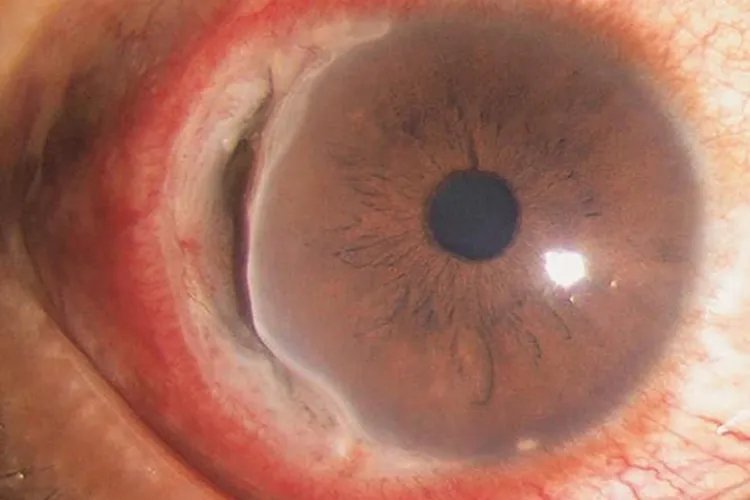

非感染性角膜炎角膜基质炎发病初期为单侧,早期可见典型的扇形或弥漫性角膜炎症浸润,可伴有或不伴有角膜后沉着物。

神经麻痹性角膜炎病变早期,暴露于睑裂部位的角膜上皮出现点状脱落,逐渐扩展成片状上皮缺损,甚至出现大片无上皮区域,继之形成溃疡。

免疫性角膜炎蚕食性角膜炎是最典型、最有代表性的免疫性角膜炎。蚕食性角膜炎病变初期,周边部角膜出现浅基质层浸润,常位于角膜内侧或外侧,随后浸润区出现角膜上皮缺损,继而形成溃疡。